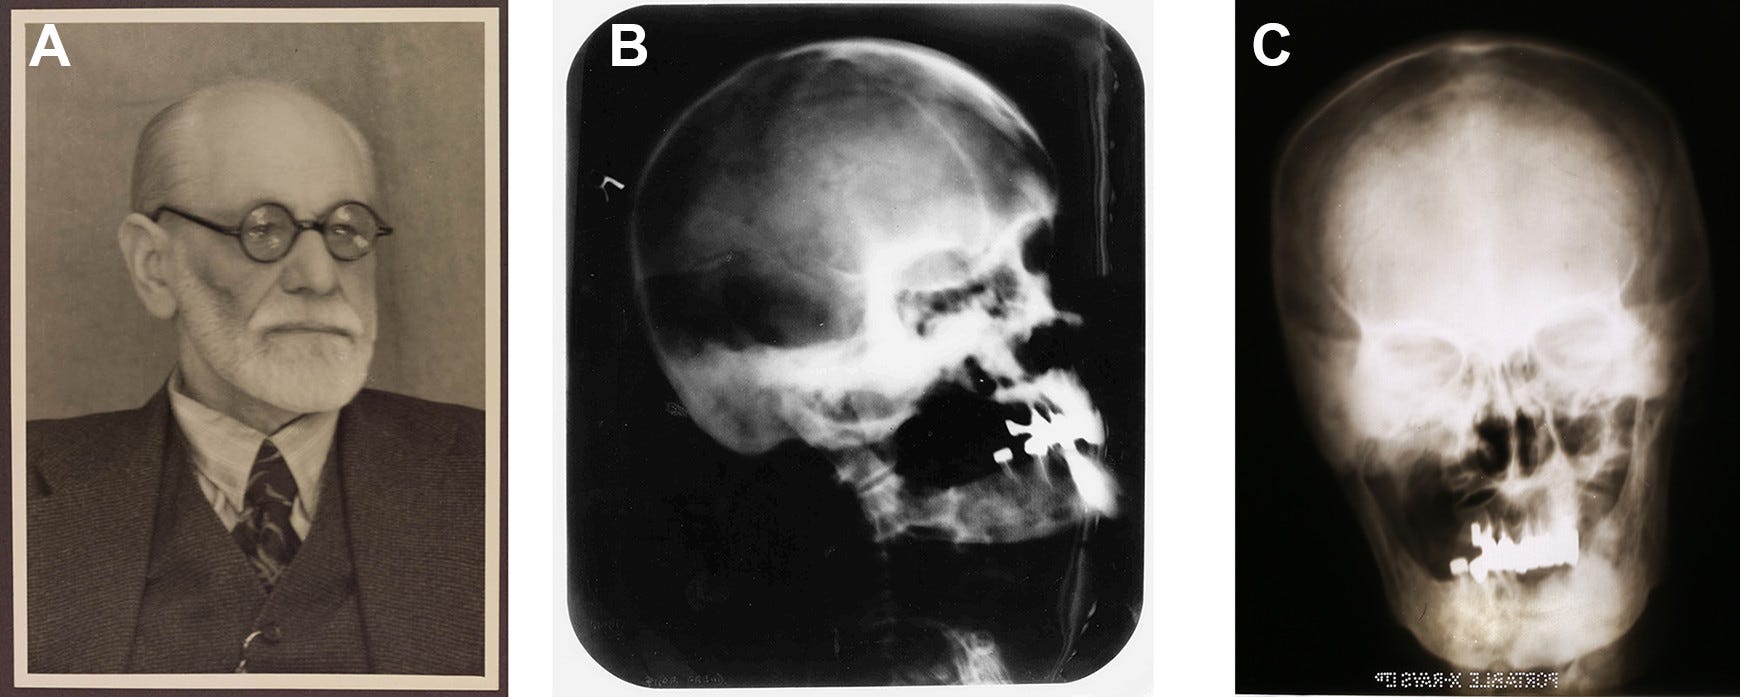

Если в 1845 году британский хирург заявлял, что «Горе и тревога числятся среди самых частых причин рака груди», это по крайней мере можно объяснить тем, что тогда никто не имел представления о том, как нарушение нормального процесса деления приводит к появлению злокачественных клеток. Но полвека спустя философ Вильгельм Райх, ученик Фрейда, нашёл удивительное объяснение тому, что отец психоанализа умер от рака ротовой полости. Райх определял рак как «болезнь, следующую за эмоциональным самоотречением», «биоэнергетическое съёживание, утрату надежды». У него получалось, что Фрейд, будучи страстным по природе и «очень несчастливым в браке» человеком, заболел раком, «поддавшись отчаянию» — а вовсе не потому что очень много курил.